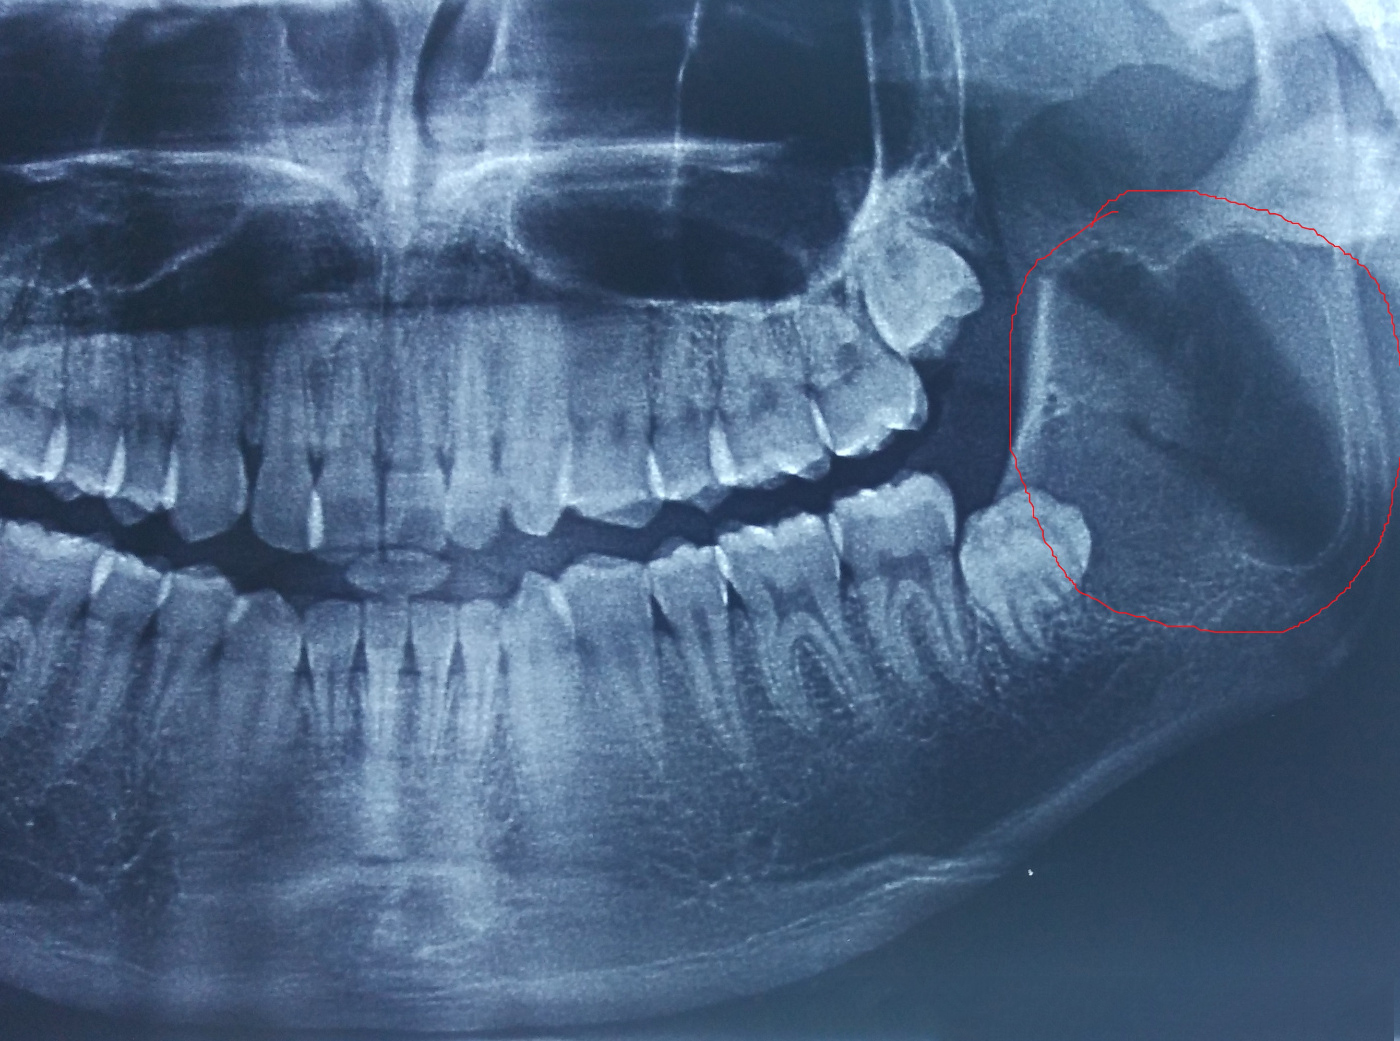

2.产生牙源性囊肿和肿瘤

如阻生牙存在,则滤泡囊也存在,虽然在多数情况下不发生变化,但也有发生囊性变而成为牙源性囊肿及肿瘤的可能性。

智齿导致的肿瘤